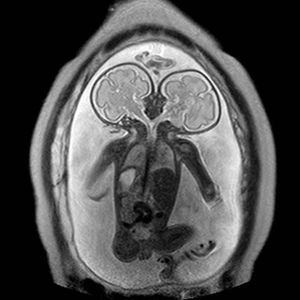

Fetus with two separate heads

MRI showed a fetus with two separate heads, a common thorax, abdomen and pelvis with a single pair of upper and lower limbs! #MRI